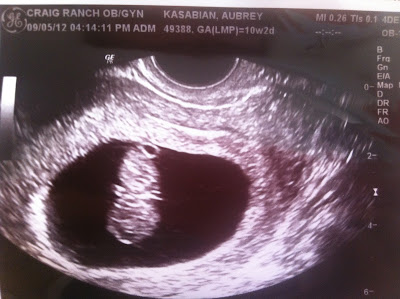

how cute is this....i am amazed at the images you get when you use sonography.  this is an image aubrey's dr. caught while doing a trans vaginal ultrasound, wednesday during her first office visit.   doesn't it look like a bat hanging upside down?......i just can't  believe what i am seeing...it's crazy to me...

back in the day you didn't  have these...so you had no clue...but now....even at 11 weeks you can see the arms, legs, heart beating etc.....wow....WOW!!

so ask me what she's having?   today it's a bat!!!  a cute bat eh?